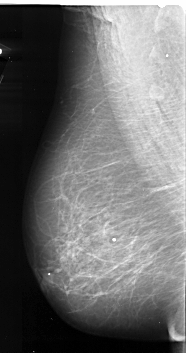

A_1085_1.RIGHT_MLO

RIGHT_MLO LINES 6286 PIXELS_PER_LINE 3001 BITS_PER_PIXEL 16 RESOLUTION 42 OVERLAY